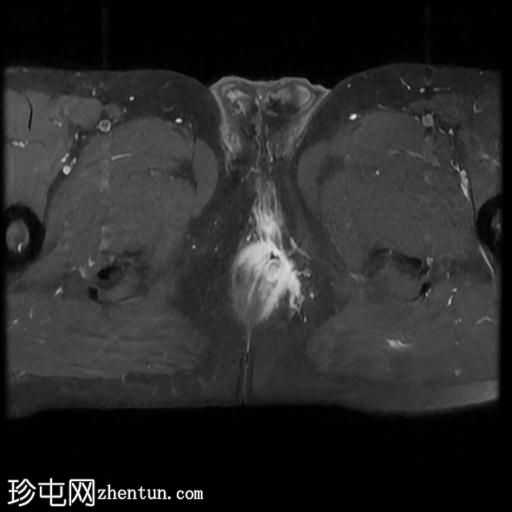

MRI

轴向位

T2

轴向位T2

脂肪饱和度

T1

轴向位T1

冠状位T1

冠状位

冠状位T2

C+脂肪饱和度

一条68毫米厚的强化通道始于左侧肛周区域,向上穿过肛门内外括约肌,在2点钟方向开口于肛管。

无脓肿形成。

MRI成像特征与所述左侧经括约肌肛周瘘相符。